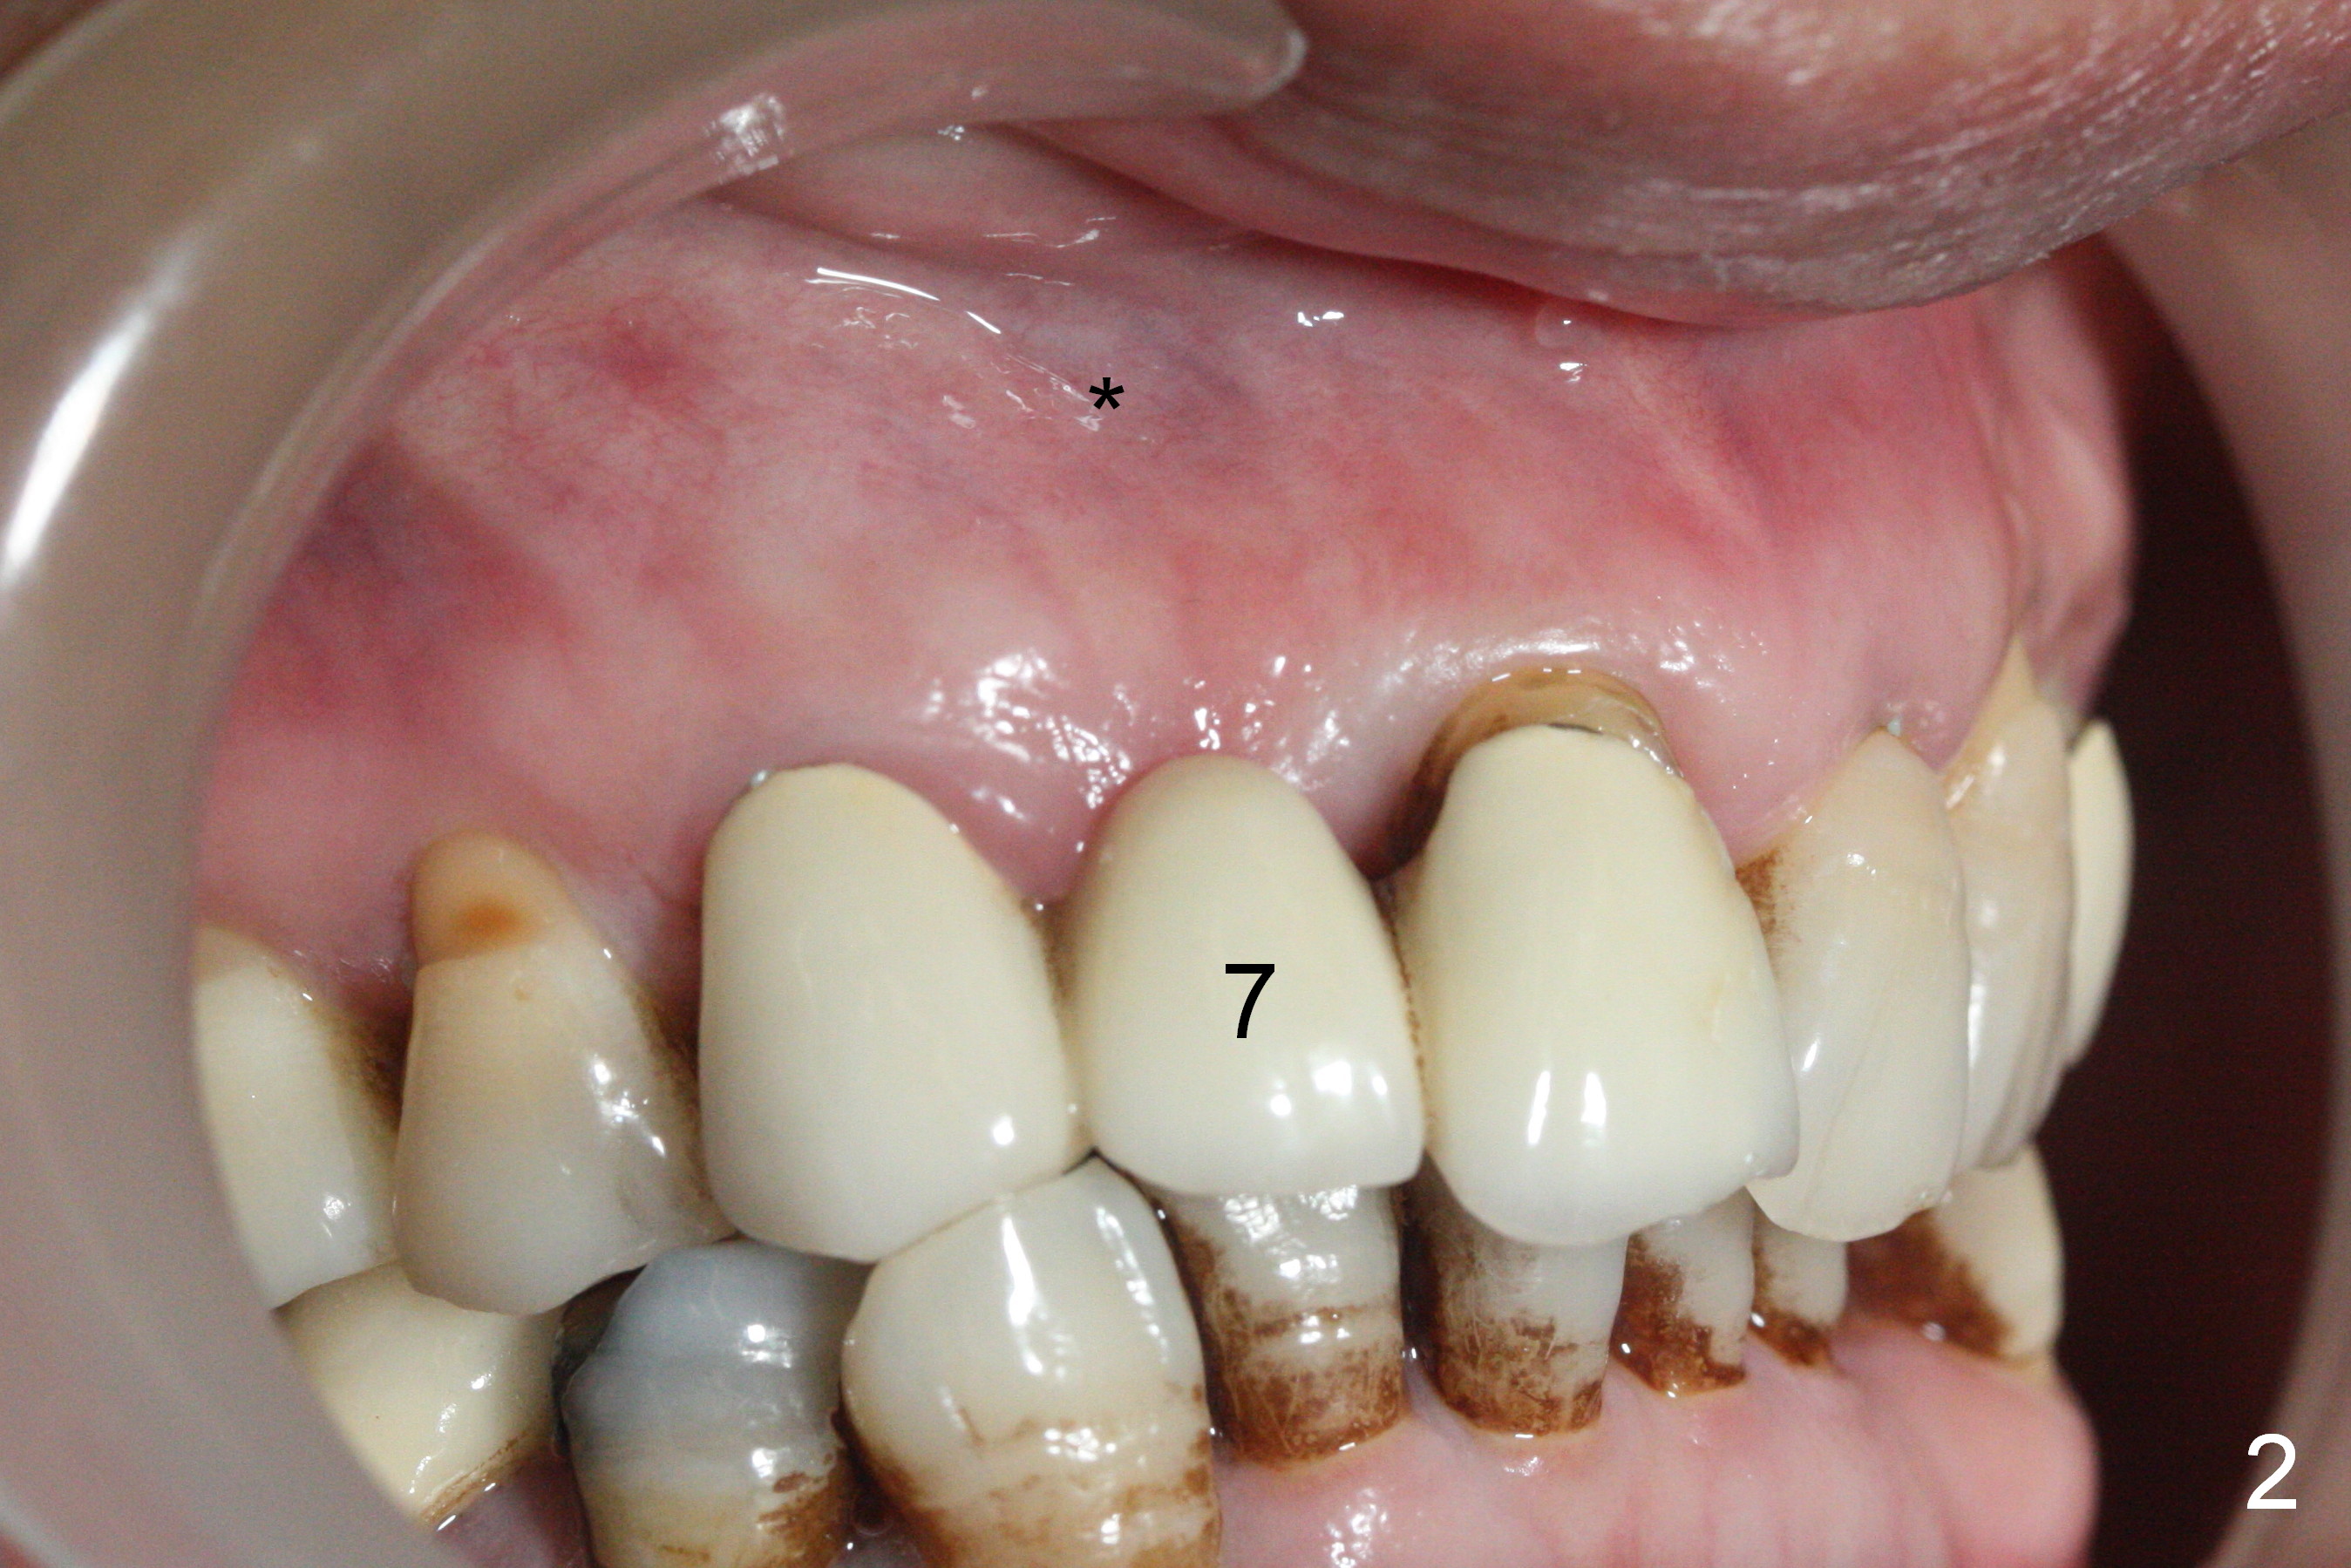

A 43-year-old woman has poor dentition including the tooth #5 (Fig.1) for RCT (Fig.3) and the teeth #2, 30 and 31 are missing. The retainer at #6 fractures (Fig.1 *). After sectioning the bridge between #7 and 8, fabricate prefabricated post at #6 if the latter is salvageable. Otherwise extract (Clindamycin) and implant (Fig.3). Anyway, a 3-mm or smaller one-piece implant is to be placed at #7 for stability and retention. Pay attention to the labial concavity at #7 (Fig.2 *). Surgical stent has been made.